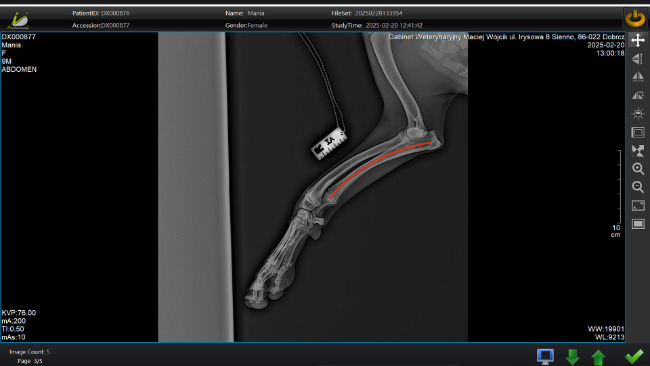

Przy standardowym RTG, gdzie sprawdzaliśmy czy nie ma dysplazji okazało się, że jej prawa łapka jest krzywa, a dodatkowo to co jest najgorsze jedna z kości przedniej prawej łapki nie rośnie. Powoduje to że druga rosnąca kość się wygina i powoduje złą pracę w stawie łokciowym i w nadgarstku. Po dwukrotnym prześwietleniu w okresie miesiąca zapadła decyzja lekarza weterynarii, że jedyną metodą aby Mania nie miała poważnych problemów w najbliższej przyszłości jest operacja przecięcia nierosnącej kości, aby druga kość mogła swobodnie urosnąć nie powodując zmian w stawie łokciowym. Musimy wykonać ten zabieg póki Mańka jeszcze rośnie, najlepiej jak najszybciej, aby nie powodować dalszych komplikacji. Jeśli nie wykonamy tego zabiegu lekarz nie wyklucza że w późniejszym etapie jej życia może dojść nawet do jej amputacji.